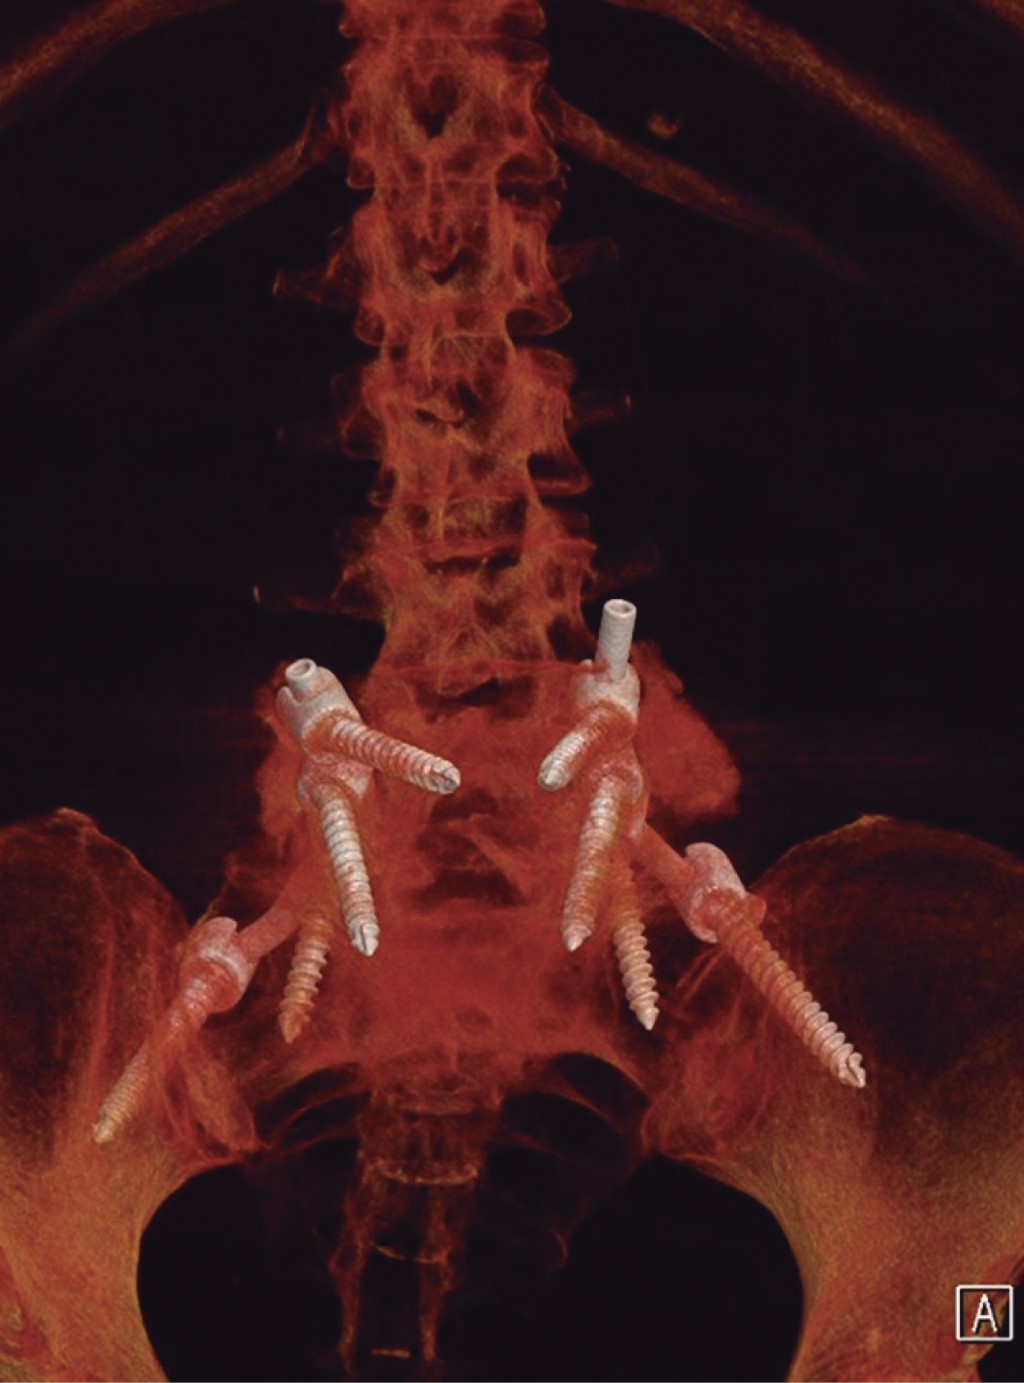

Ozone is a medical gas described since the 19th century; the ozone therapy has evolved to date in terms of its applications and its usefulness in various diseases due to its action at the molecular level and in dissimilar diseases associated with painful processes of inflammatory origin such as present in herniated discs of the spine, although the benefits of its application are currently in controversy, as well as the various complications that may occur after its application. Pneumocephalus is a complication that occurs in the background of a head injury or neurosurgery. Ozone infiltrations are used for the treatment of disc prolapse to reduce clinical symptoms. The anti-inflammatory effect of ozone is supported by its ability to oxidize compounds that contain double bonds such as arachidonic acid and prostaglandins, which are active substances with high concentrations in the inflammatory process. The appearance of pneumoencephalus and arachnoiditis chemical after epidural injection and also with ozone infiltrations is a rare complication but it has been described in recent years as a devastating post-application complication. Arachnoiditis can present as sensory and motor deficits, paresthesias, transient radicular neurological syndrome (TRNS), cauda equina syndrome, and conus medullaris. In relation to arachnoiditis, cases as severe as cauda equina syndrome after spinal anaesthesia, and more benign such as TSNR have been described, characterized by low back pain that radiates to the lower extremities, and not associated with motor deficits. neither sensitive, nor sphincter incontinence, which appears in the first 24 hours, which can last several days, and which resolves without neurological sequelae. Understanding the pathophysiology is important to assess and diagnose this type of neurological complications, especially in patients with disc disease who have undergone this type of treatment. The purpose of this report is to present the case of a patient with disc disease with the presence of radiculopathy who underwent infiltration by ozone therapy, who immediately presented complications such as pneumoencephalus and chemical arachnoiditis that led her to remain hospitalized in intensive care and present cauda equina syndrome.REFERENCES